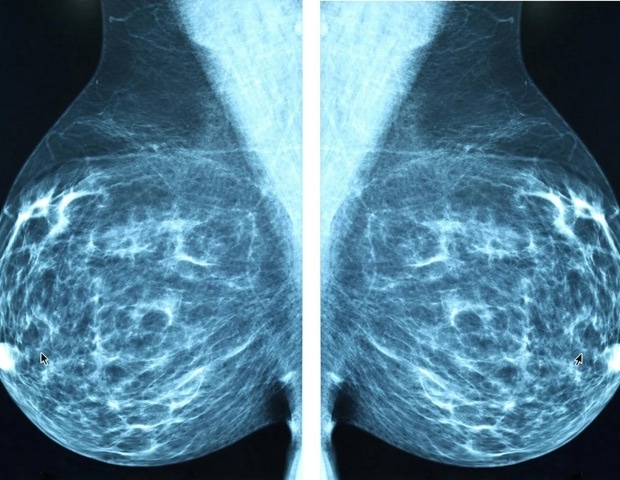

‘A second set of eyes’: AI-supported breast cancer screening spots more cancers earlier, landmark trial finds

Science

Really Simple SyndicationFebruary 7, 2026

A clinical trial shows that AI-assisted mammography can detect more cases of dangerous cancer and reduce missed diagnoses.